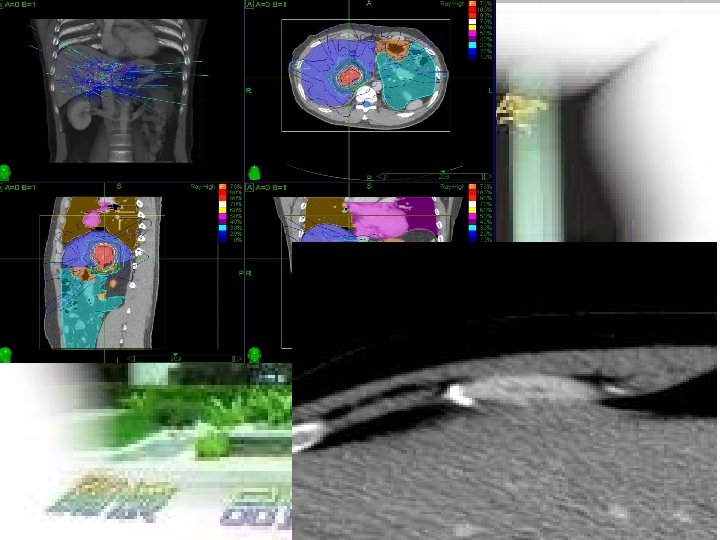

T 7 -005 Survival and Prognostic Factors for Patients with Advanced Hepatocellular Carcinoma after Stereotactic Ablative Radiotherapy Wen-Yen Huang (黃文� ), Cheng-Hsiang Lo, Jen-Fu Yang, Ming-Yueh Liu, Yee-Min Jen, Chun-Shu Lin, Hsing-Lung Chao Department of Radiation Oncology Tri-Service General Hospital

PURPOSE ¢ To evaluate the survival outcomes and prognostic factors for patients with BCLC stage C HCC after SABR.

MATERIALS &METHODS ¢ A retrospective cohort study ¢ Between December 2007 and July 2015 ¢ BCLC stage C disease ¢ Child-Turcotte-Pugh class A–B